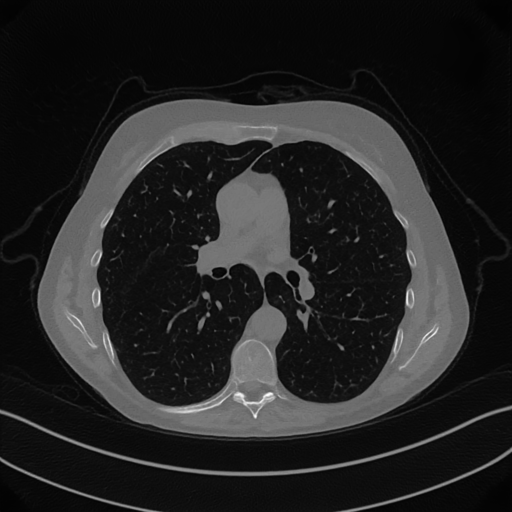

Here we present the results of RISING applied to the Mayo data set introduced in paragraph 4.1. As previously mentioned, we consider two sparse-view CT geometries, namely P360,360subscript𝑃360360P_{360,360} and P360,180subscript𝑃360180P_{360,180}. In Figure 4 we report the results for the P360,360subscript𝑃360360P_{360,360} protocol, achieved on one image of our test set. The top-left image represents the xRIS=x(15)subscript𝑥𝑅𝐼𝑆superscript𝑥15x_{RIS}=x^{(15)} reconstruction. Even if only a small number of iterations are performed, the main structures of the abdomen are visible; however, the image is still blurry. In the xISsubscript𝑥𝐼𝑆x_{IS} image, shown in the upper-right corner, we notice that the TV regularizer has acted to totally eliminate the artifacts and noise, improving the uniformity of the image in the inner structures. When compared to the ground-truth solution in Figure 2, the contours of the details in xISsubscript𝑥𝐼𝑆x_{IS} appear slightly jagged, differently from xGTsubscript𝑥𝐺𝑇x_{GT} where they are neat but, usually, corrupted by artifacts. The bottom row of Figure 4 shows the two xLPPsubscript𝑥𝐿𝑃𝑃x_{LPP} and xINGsubscript𝑥𝐼𝑁𝐺x_{ING} images, respectively from left to right. It is evident that xLPPsubscript𝑥𝐿𝑃𝑃x_{LPP} has retrieved many details but it presents noisy components, reflecting the features of its target image xGTsubscript𝑥𝐺𝑇x_{GT}. Our solution xINGsubscript𝑥𝐼𝑁𝐺x_{ING} is less corrupted, since the low-contrast regions are correctly preserved and the noise is not visible. These observations are confirmed by Figure 5, which plots the intensity profiles taken over the red line in the second crop (Figure 2). In our approach (on the right) the CNN has accurately learnt the f𝑓f map of (8) and the xINGsubscript𝑥𝐼𝑁𝐺x_{ING} red profile mostly overlaps the black one. On the contrary, the xLPPsubscript𝑥𝐿𝑃𝑃x_{LPP} profile (on the left) is more distant from its target reference.

Figure 4: Results on a test image from the Mayo data set, under the P360,360subscript𝑃360360P_{360,360} CT protocol. Top-left: xRISsubscript𝑥𝑅𝐼𝑆x_{RIS}; top-right: xISsubscript𝑥𝐼𝑆x_{IS}; bottom-left: xLPPsubscript𝑥𝐿𝑃𝑃x_{LPP}; bottom-right: xINGsubscript𝑥𝐼𝑁𝐺x_{ING}.